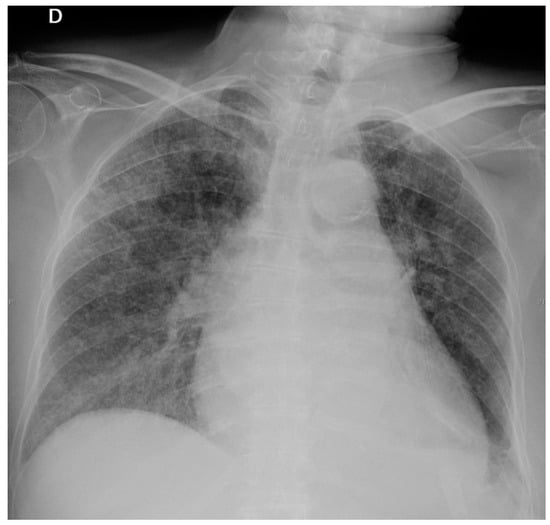

After bronchoscopy, steroids were administered (methylprednisolone 0.5 mg/kg) but respiratory distress increased (Figure 4) and the patient died five days later.

Figure 4.

Chest X-ray on 16th day: Extensive bilateral reticulo-nodular infiltrates.